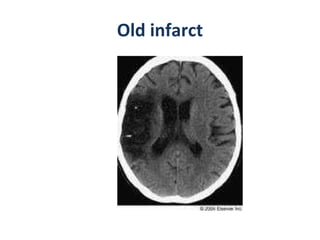

CT-chronic infarct Plain ct  Focal, well-delineated low-attenuation areas in affected vascular distribution sulci become prominent; ipsilateral ventricle enlarges Dystrophic Ca++ may occur in infarcted brain but is very rare CECT :  No enhancement

Old infarct

CT-chronic infarct Plainct Focal, well-delineated low-attenuation areas in affected vascular distribution sulci become prominent; ipsilateral ventricle enlarges Dystrophic Ca++ may occur in infarcted brain but is very rare CECT : No enhancement